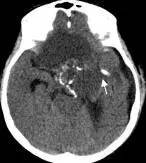

鉴于肿瘤体积超大,而且患儿间断出现意识障碍,直接作手术完全切除肿瘤的难度很大,为降低手术风险,所以我们采用先穿刺肿瘤囊减少肿瘤体积,降低颅压,二期手术争取完全切除肿瘤的策略。行肿瘤囊肿穿刺后,引流出约100多毫升囊液,肿瘤体积显著变小,见图3、图4。

图4.肿瘤囊穿刺手术后肿瘤体积减小

白色箭头示引流管